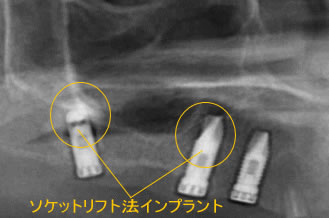

ソケットリフトとは、そのように上顎の骨の厚みが薄い場合に、厚みを増すために行われる方法です。

上顎洞のインプラントを植える穴(もとの歯が抜けた部分)から、骨のもととなる物質を入れて、 少しずつ上顎洞粘膜(シュナイダー膜)を押し上げていきます。

押し上げられた粘膜と、その間に詰まった骨のもととなる物質の分だけ、骨の厚みを増すことができます。

骨のもととなる物質が固まって、完全に骨になるのを待ってから、インプラントを行います。